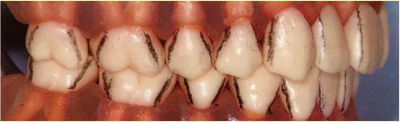

牙周袋深度測定法

1、測定哪個位置?

1點·4點·6點法

牙周袋深度的測定方法有1點法、4點法、6點法、臨床上基本檢查選用1點法、精密檢查選用6點法。

進(jìn)行牙周治療時,適合選用4點法或6點法收集檢查資料。